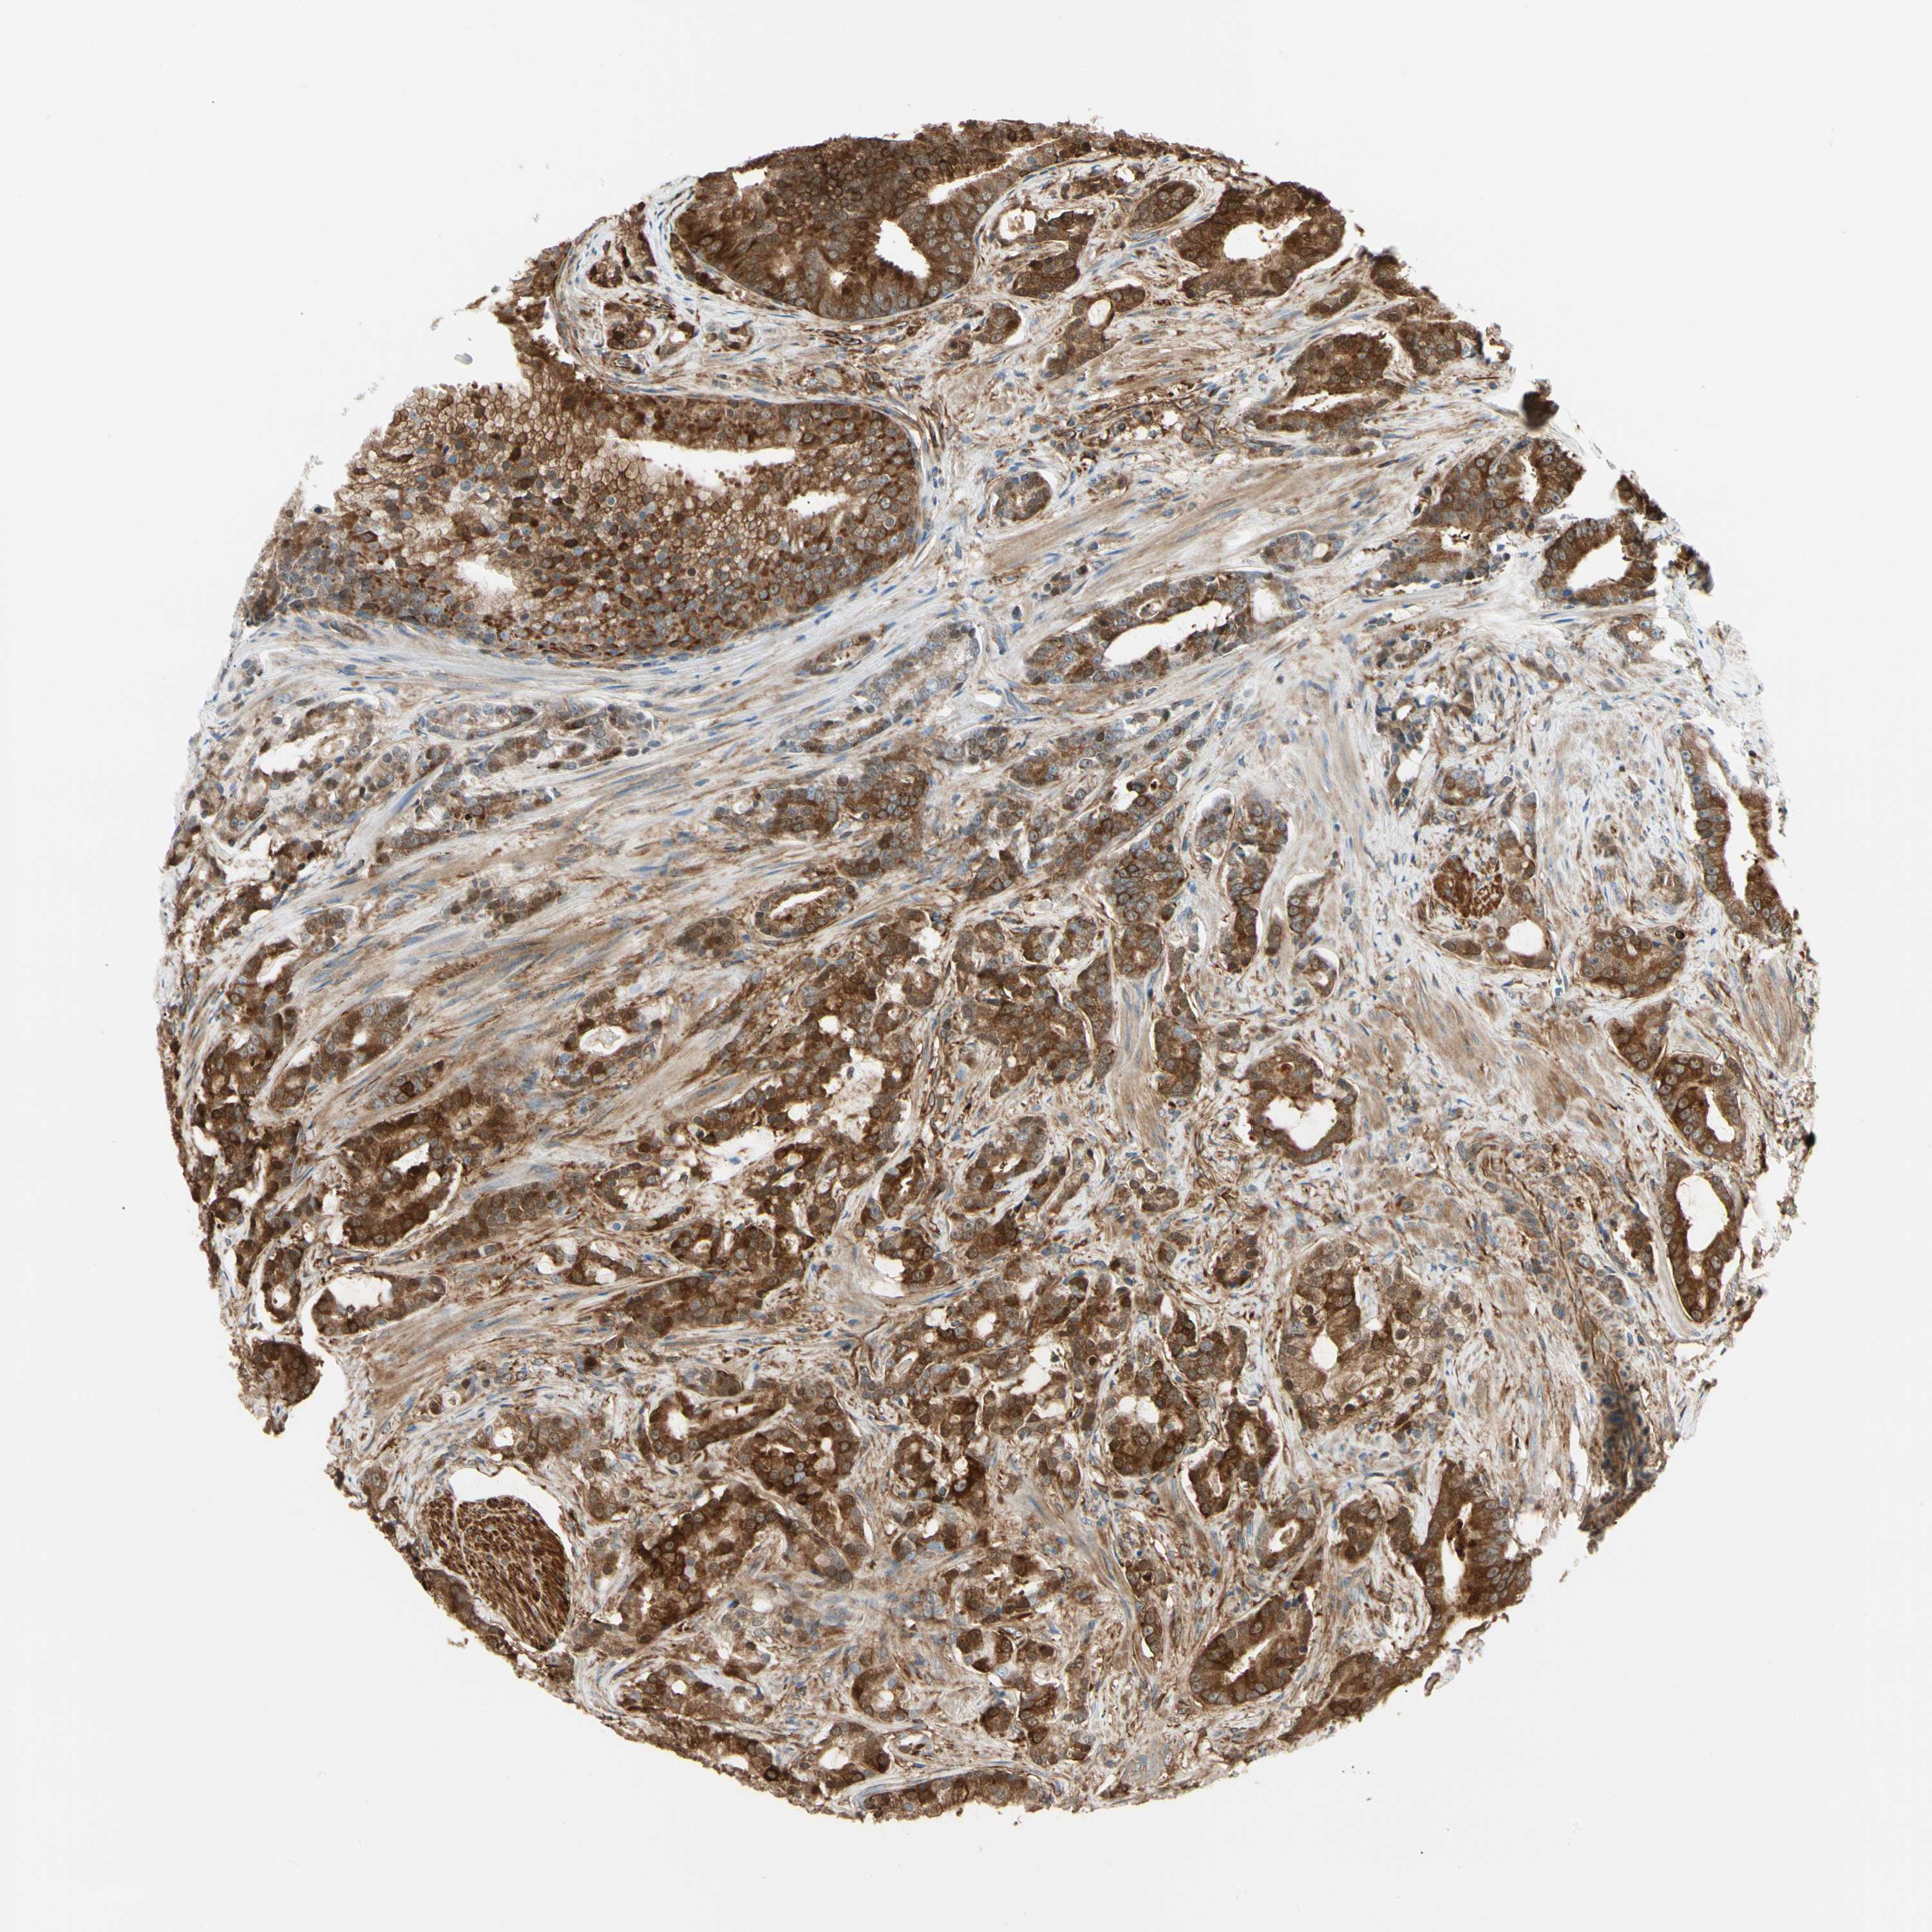

PROSTATE CANCER - Protein expressioni

A mouse-over function shows sample information and annotation data. Click on an image to view it in a full screen mode. Samples can be filtered based on level of antibody staining by selecting one or several of the following categories: high, medium, low and not detected. The assay and annotation is described here.

Antibody stainingi

Antibody staining in the annotated cell types in the current human tissue is reported as not detected, low, medium, or high, based on conventional immunohistochemistry profiling in selected tissues. This score is based on the combination of the staining intensity and fraction of stained cells.

Each image is clickable and will lead to virtual microscopy that enables deeper exploration of all samples and also displays staining intensity scores, fraction scores and subcellular localization as well as patient and tissue information for each sample.

Antibody CAB008623

Staining

High

Medium

Low

Not detected

Intensity

Strong

Moderate

Weak

Negative

Quantity

>75%

75%-25%

<25%

None

Location

Nuclear

Cytoplasmic/membranous

Cytoplasmic/membranous,nuclear

Adenocarcinoma, Low grade

Adenocarcinoma, High grade